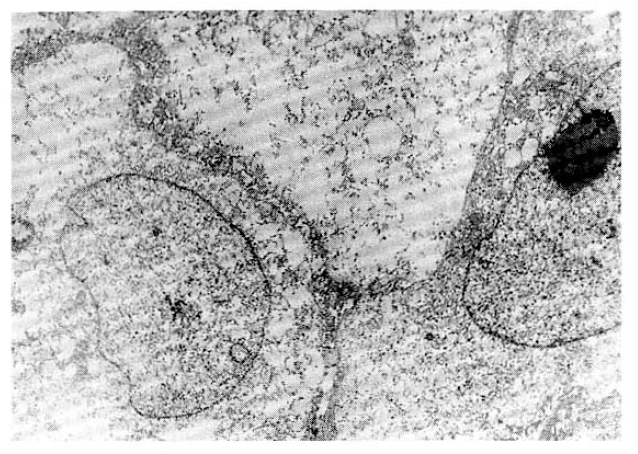

Fig. 5.

Electromicroscopy shows that the tumor cell has convoluted nuclei with prominent nucleoli and sparse intracytoplasmic organelles.

Laboratory evaluation revealed hemoglobin of 7.4g/dl, hematocrit of 22.4 percent, leukocyte of 14,600/mm3 with 66 percent neutrophils and 8 percent lymphocytes and platelet 300,000/mm3. The erythrocyte sedimentation rate was 71 mm/hour. Results of serum chemistry test were normal with exception of LDH 1003.3IU/I, BUN 29.9mg/dl, creatinine 1.9mg/dl. The electrocardiography was normal. Radiologic examination of chest revealed fibrostreaky densities in right upper lobe and CT scan of abdomen showed no intra-abdominal lymphadenopathy. Biopsy of cutaneous lesions on anterior chest wall and bone marrow aspiration and biopsy were performed. Light microscopic examination of skin specimen showed that the dermis was diffusely infiltrated with large pleomorphic tumor cells, which were strongly positive for Ki-1 immunohistochemical stain (Fig. 3, 4). Electromicroscopic examination revealed convoluted nuclei with prominent nuclei and sparse intracytoplasmic organelles (Fig. 5). Bone marrow aspiration and biopsy showed a focus of collection of atypical cells with complete necrosis, suspicious for involvement of malignant lymphoma. On diagnosis of relapsed Ki-1-positive anaplastic lymphoma stage IV, we performed salvage chemotherapy with cisplatin, dexamethasone, mitoxantrone and etoposide but, unfortunately, he died of persistent pancytopenia, followed by sepsis.